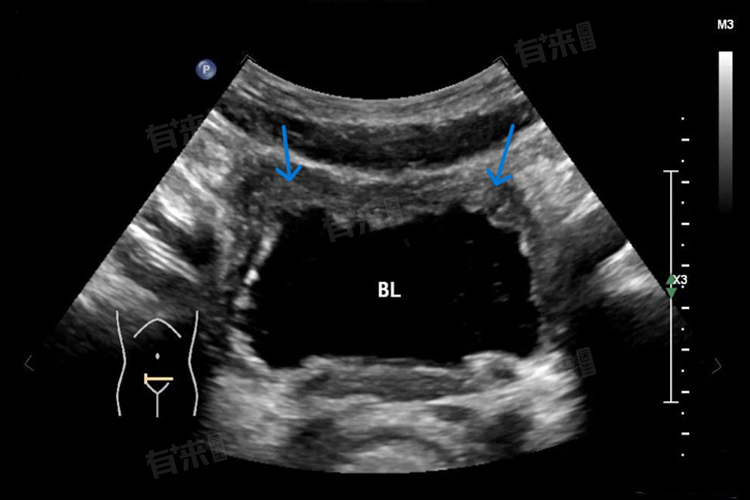

膀胱壁增厚是指膀胱壁的厚度超过正常范围,通常大于5毫米,这一现象可能由多种因素引起,包括生理性和病理性因素。此时不一定需要治疗,需根据具体情况综合评估。

- 尿潴留:长期尿潴留会导致膀胱壁组织缺血缺氧、水肿和炎症反应,进而使膀胱壁增厚,需解除尿潴留,恢复膀胱正常功能。